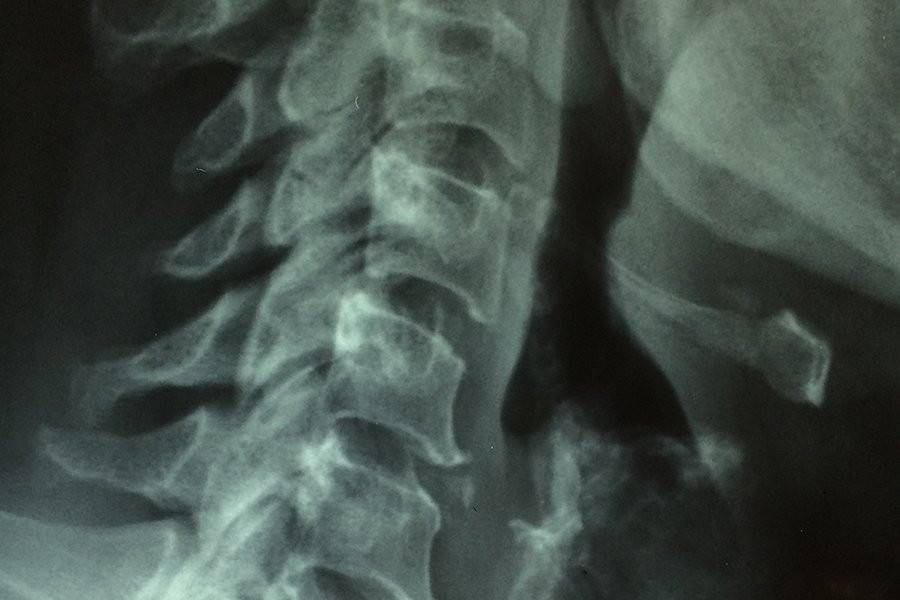

Образование рубцов после травмы спинного мозга оказалось более сложным процессом

Новое исследование показывает, что образование рубцов после травм спинного мозга является более сложным процессом, чем считалось ранее. Ученые определили два типа периваскулярных клеток, которые играют ключевую роль в формировании рубцовой ткани, которая препятствует регенерации нервов и функциональному восстановлению. Эти результаты, опубликованные в журнале Nature Neuroscience, также актуальны для других травм головного и спинного мозга и могут привести к разработке таргетной терапии для уменьшения рубцов и улучшения результатов.

Центральная нервная система (ЦНС) имеет очень ограниченные способности к исцелению. Травмы в результате дорожно-транспортных происшествий, спортивных инцидентов или аутоиммунных заболеваний, таких как рассеянный склероз, часто приводят к постоянным функциональным нарушениям. Независимо от причины травмы, организм реагирует формированием границы вокруг поврежденной ткани, которая в конечном итоге становится постоянной рубцовой тканью.

Хотя рубцовая ткань запечатывает поврежденный участок, она также предотвращает функциональное восстановление. После травм спинного мозга рубцовая ткань блокирует регенерацию нервных волокон, соединяющих головной мозг с телом, что приводит к параличу после тяжелых травм.